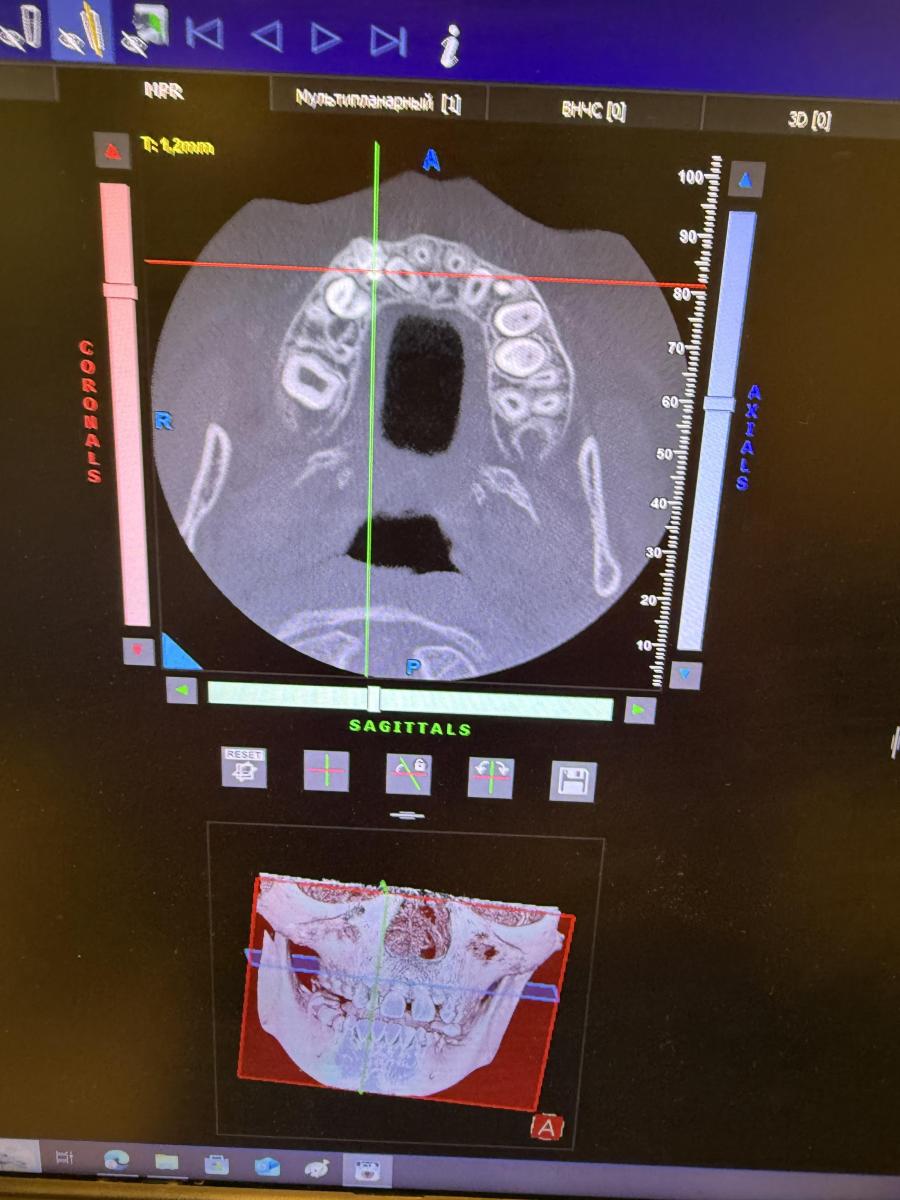

Здравствуйте, Ребекку 7 лет. Отсутствуют нижние зачатки 5 зубов. Верхний зачаток пятерки в недоразвитом состоянии и перевернут . Что с ним будет? Возможно ли что вырастет как надо? И основной вопрос- верхний клык (снимок прилагаю) между молочным и коренным обнаружено какое-то образование- это лишний зуб? Как его удалять? Вырывать молочный клык сейчас , далее удалять лишний и уже после ждать прорезывания постоянного? Или ждать пока молочный сам выпадет?